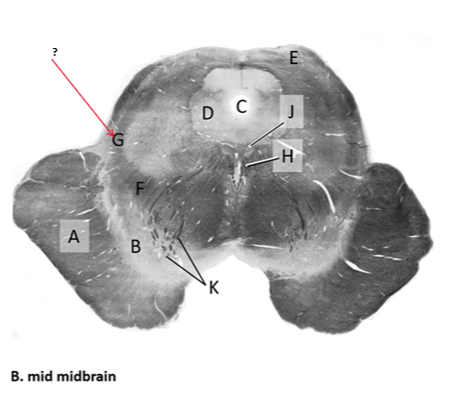

Name this and state its function.

Tectum.

Name this and its divisions+ function?

Substantia nigra.

Cerebral aqueduct.

Crus cerebri.

Medial Lemniscus.

Name this, what is it and state its function.

Lateral lemniscus.

Name this, state its function[2 marks] and how it goes about its function[4 marks].

Medial longitudinal lemniscus.

How?

Oculomotor nucleus.

Name this, state its function[3 marks] and cells involved contributing to function.

Periaqueductal grey.

Root fibres of Oculomotor nerves(CN III).